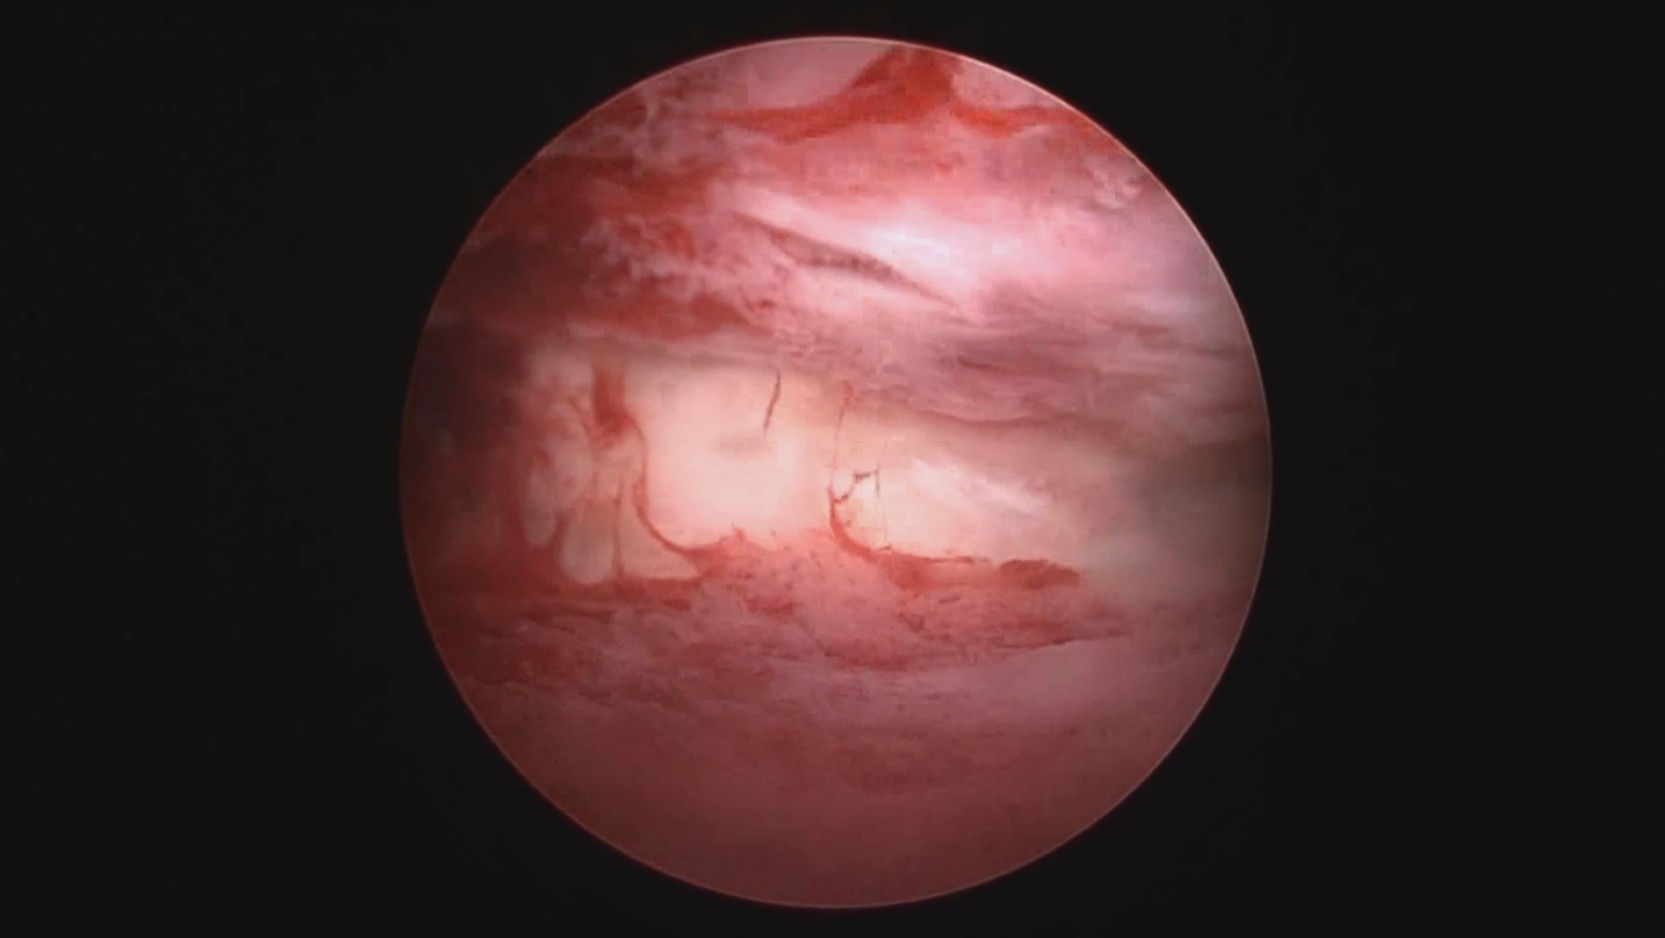

患者39岁,G4P2,顺产2次。2025年2月因异常子宫出血,阴道出血淋漓不净1+月行宫腔镜检查及内膜活检,病检为子宫内膜增生(无非典型)伴息肉形成。2025年3月,行经第3天,月经量大伴腹痛,要求放置曼月乐并固定。宫腔镜见内膜杂乱,脱落不全,吸刮内膜送病检,4-0不可吸收线将曼月乐环缝合固定于宫腔上段后壁。术中打结、推结很困难,放弃打结,留较长线尾在宫颈管,必要时可牵拉线尾调整节育环位置,只要缝合到子宫肌层,肌肉的卡压阻力可以起到固定作用,继续探索不用打结推结的固定方法。术后多次复查B超,子宫偏大,7.7cm*6.6cm*7.8cm,环顶端距宫底3cm。